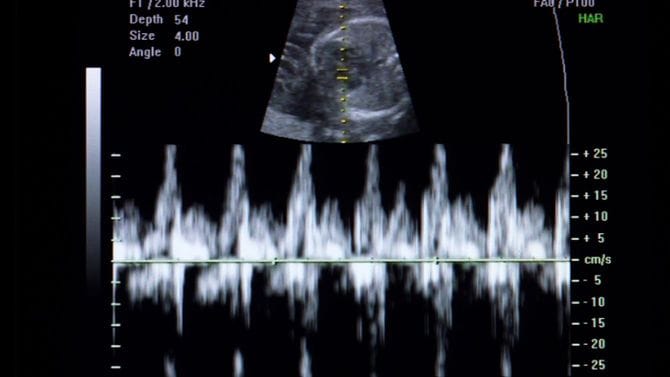

ハンガリーの中絶手術は公立の医療機関なら2万円未満で受けられ、社会的に困難な人などは無料だ。10万円前後する日本より安いが、手術前にカウンセリングで胎児の心音を聞かなければいけない。これについては国内外で批判の声が上がっている。